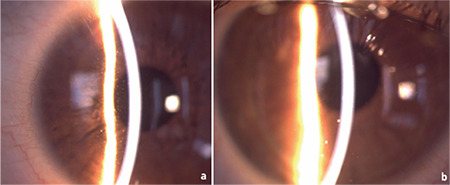

Results: The study included 19 eyes of 10 patients (6 female/4 male). The mean age was 13.5±2.4 years (range: 8-16 years). The mean follow-up duration was 13.5±6.1 months (range: 6-24 months). All patients presented with anterior uveitis. Anterior uveitis was bilateral in 9 patients (90%) and unilateral in 1 patient (10%). Posterior segment findings were normal in 8 patients (80%), and bilateral optic disc edema was observed in only 2 patients (20%). None of the patients had a previous SARS-CoV-2 infection and/or vaccination history. The SARS-CoV-2 PCR test was negative in all patients at presentation. The SARS-CoV-2 IgG antibody test was reactive in 7 patients (70%). Recurrent uveitis developed in 8 patients (80%) during follow-up. Systemic immunomodulatory therapy was required for the control of ocular inflammation in 7 patients (70%) with severe uveitis flare-ups.